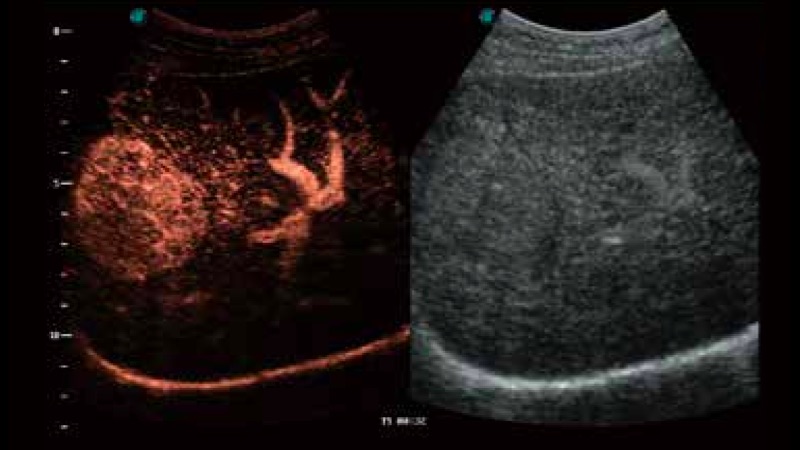

開立醫(yī)療通過不斷的技術(shù)創(chuàng)新,為大眾的生命健康提供持續(xù)關(guān)愛。P12 Plus采用全新一代超聲成像平臺,新平臺旨在將真實還原組織解剖結(jié)構(gòu)作為首要目標(biāo)。平臺采用全新集成化硬件模塊,搭載新一代芯片,系統(tǒng)性能得到大幅提升,為您的診斷提供了豐富的臨床信息。優(yōu)異的圖像表現(xiàn),豐富的探頭配置,全面的應(yīng)用功能,為您日常診斷提供了可靠的助手。

彩色多普勒超聲診斷系統(tǒng)